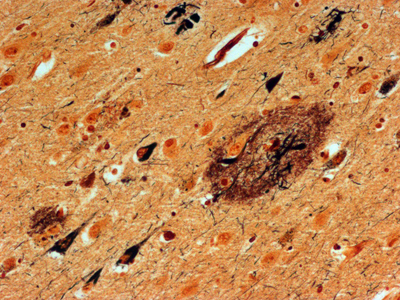

Before AIDS was even proven to be caused by a viral infection, it was clearly associated with severe neurologic disease. Beyond the devastating opportunistic infections related to severe immunosuppression, late-stage AIDS patients also exhibited a unique dementia. In retrospect, the histopathology of AIDS dementia was exactly what should have been expected for a macrophage tropic virus in a patient with severe immunosuppression, minimal to no lymphocyte infiltration in the context of abundant virus [25] (Figure 5). Indeed, the concentration of virus in the CNS exceeded that in lymphoid organs [26]. The big mystery that has yet to be solved is, How did infection of microglia in the absence of neuroglial infection lead to a clinical dementia [27]? It has been hypothesized that infected microglia either produced a neurotoxin (e.g., quinolinic acid [28]) or were unable to carry out critical physiological functions that non-infected microglia normally perform (e.g., synaptic stripping). Hypotheses range from remote or local responses to immunologic stimulation to hypothesized abortive infection of astrocytes. Before intensive investigation could elucidate the pathogenesis of AIDS dementia, highly effective anti-retroviral therapy eradicated HIV encephalitis. While HIV infected individuals still experience neurologic symptoms of unknown etiology, AIDS dementia, like syphilis dementia, disappeared.

Figure 5A. Low power H&E-stained section of cortical tissue from a patient with HIV encephalitis.

Figure 5B. Higher power H&E-stained section showing a multinucleated giant cell.